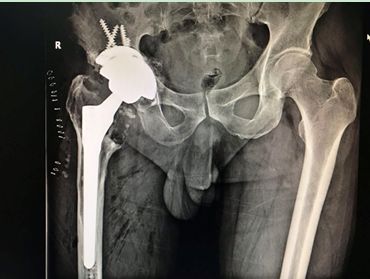

術后X線:骨小梁填充塊重建髖臼骨缺損

通過術后X線可以看出,患者假體安放位置良好,肢體長度恢復,手術成功。目前該患者恢復良好,術后第二天已經可在助行器保護下下床行走。